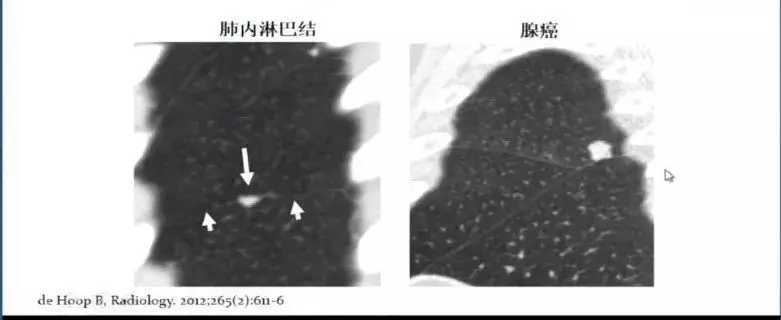

4. 肺内淋巴结

肺内淋巴结在体检中也较为常见,肺内淋巴结的影像特点主要以下特点:贴近胸膜;位于肺小叶的不同部位,其形态多变,三角形、圆形、扁圆形、梭形、五角形等都是常见的肺内淋巴结形状。

肺内淋巴结通常需要与肺腺癌进行鉴别诊断,腺癌结节通常中心位于肺内,这一特点能够与肺内淋巴结贴近胸膜的特点进行区分。

图7 肺内淋巴结鉴别诊断